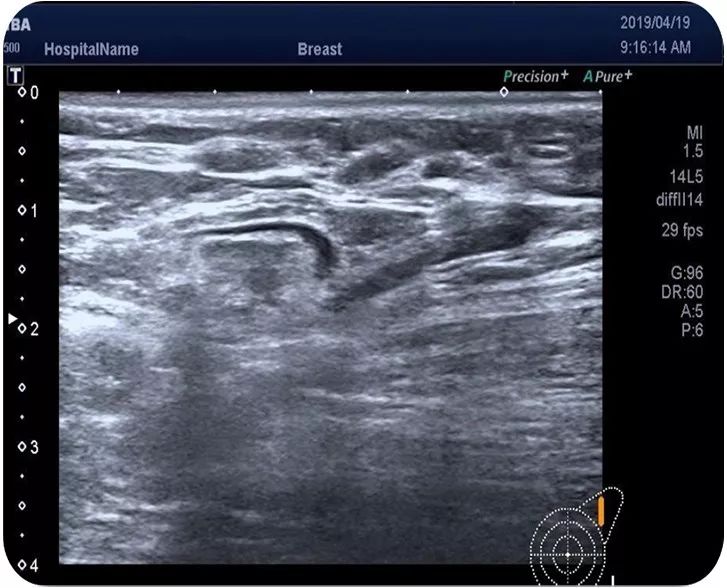

乳腺B超:左乳低回声,大小约4.5*3.5*2.2cm,边界欠清,形态不规整,内回声不均匀,内可见多发点状强回声(BI-RADS 4C类),左侧腋窝探及肿大淋巴结,皮髓质可辨。

乳腺超声:左乳上象限探及低回声结节,大小约3.2*2.2*3.8cm,边界不清,形态不规则,可见点状强回声,右乳未见异常肿块回声。左侧腋窝探及一皮髓质可辨的淋巴结。